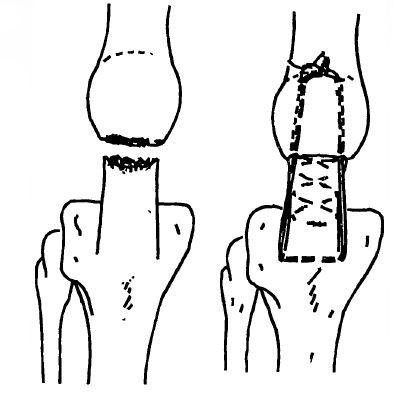

Для замещения дефекта в разгибательном аппарате, образовавшегося после резекции нижней трети надколенника, нами разработаны два способа аутопластики. Первый способ заключается в пластике дефекта лоскутом на дистальной ножке из сухожилия прямой головки ЧГМ. Лоскут шириной 1,5 см и толщиной 0,5 см отворачивают вниз и вшивают узловыми швами в расщеп связки. Его «защищают» блокирующей петлей, проводимой через поперечные каналы под бугристостью большеберцовой кости и в дистальной части сохраненного фрагмента. При этом для защиты шва достаточно низвести надколенник петлей на 1—2 мм (рис. 2, а).

При втором способе из средней части связки надколенника во всю толщу выкраивают свободный трансплантат с костным блоком от бугристости большеберцовой кости на конце. Размер блока 1,5X1 см. В торце оставшегося фрагмента надколенника максимально близко к его передней поверхности цилиндрической зубной фрезой создают полость, соответствующую по форме и размеру костному блоку на конце аутотрансплантата. Последний переворачивают на 180°, костный блок внедряют в образованную полость так, чтобы он оказался погруженным в нее целиком. Сухожильную часть трансплантата сшивают узловыми швами с оставшимися боковыми частями связки, а костный блок, погруженный в фрагмент надколенника, фиксируют одним — двумя винтами АО. Дополнительно накладывают блокирующую проволочную петлю, как и при первом способе (рис. 2,6). Оба эти способа с успехом применены у 3 больных после резекции дистальной трети надколенника в связи с многооскольчатыми переломами.

Рис. 2. Схема аутопластики дефекта разгибательного аппарата после резекции нижней трети надколенника.

а — пластика лоскутом из сухожилия прямой мышцы с дополнительным блокированием; б — пластика свободным перевернутым трансплантатом из средней части связки надколенника с костным блоком на конце.